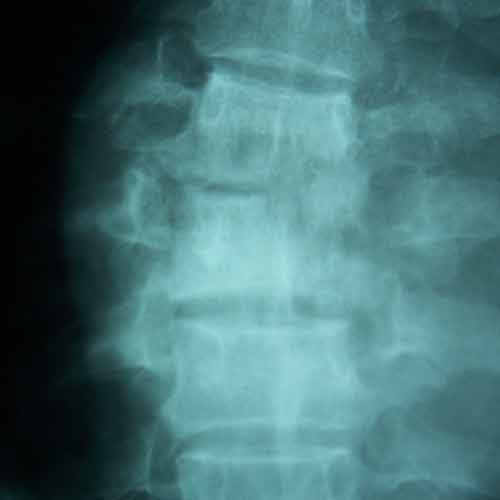

Pre-op Lateral